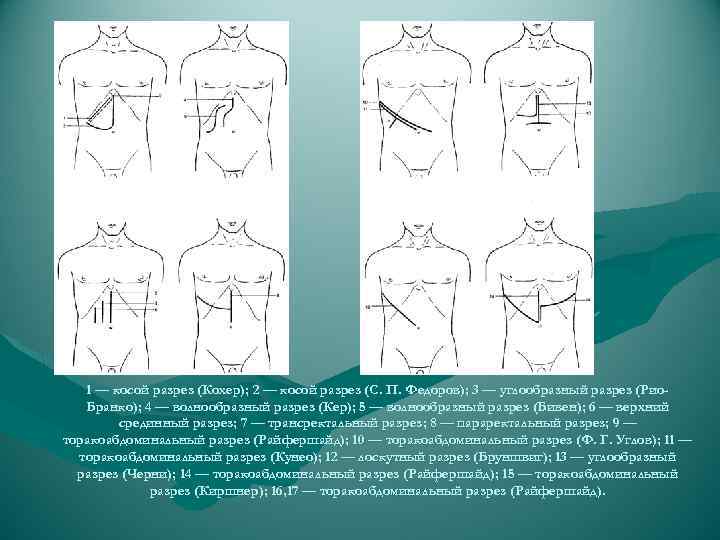

1 — косой разрез (Кохер); 2 — косой разрез (С. П. Федоров); 3 — углообразный разрез (Рио. Бранко); 4 — волнообразный разрез (Кер); 5 — волнообразный разрез (Бивен); 6 — верхний срединный разрез; 7 — трансректальный разрез; 8 — параректальный разрез; 9 — торакоабдоминальный разрез (Райфершайд); 10 — торакоабдоминальный разрез (Ф. Г. Углов); 11 — торакоабдоминальный разрез (Кунео); 12 — лоскутный разрез (Бруншвиг); 13 — углообразный разрез (Черни); 14 — торакоабдоминальный разрез (Райфершайд); 15 — торакоабдоминальный разрез (Киршнер); 16, 17 — торакоабдоминальный разрез (Райфершайд).

1 — косой разрез (Кохер); 2 — косой разрез (С. П. Федоров); 3 — углообразный разрез (Рио. Бранко); 4 — волнообразный разрез (Кер); 5 — волнообразный разрез (Бивен); 6 — верхний срединный разрез; 7 — трансректальный разрез; 8 — параректальный разрез; 9 — торакоабдоминальный разрез (Райфершайд); 10 — торакоабдоминальный разрез (Ф. Г. Углов); 11 — торакоабдоминальный разрез (Кунео); 12 — лоскутный разрез (Бруншвиг); 13 — углообразный разрез (Черни); 14 — торакоабдоминальный разрез (Райфершайд); 15 — торакоабдоминальный разрез (Киршнер); 16, 17 — торакоабдоминальный разрез (Райфершайд).